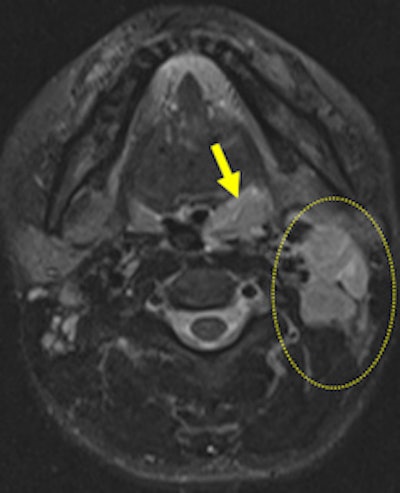

The same patient as seen on postcontrast fat-saturated T1 weighted (left), respectively. Left-sided peripherally enhanced, mostly necrotic, lymphadenopathies (dashed circle) are present on level 2 on axial short tau inversion-recovery and axial postcontrast fat-saturated T1-weighted images. Accompanying minimal signal intensity change and increased thickness of neighboring soft-tissue planes are seen as well. Remarkable restriction of diffusion is illustrated within lyphadenopathies and left palatine tonsil (ADC = 0.82 mm/sn2) (right).The clinical manifestation of tularemia may vary from asymptomatic illness to fulminant toxemia with septic shock, and presentation is dependent on the organism and the route of transmission. Tularemia is traditionally classified into the following clinical types, depending on the route of transmission: ulceroglandular (80%), glandular (15%), oropharyngeal (less than 5%), oculoglandular (1%), typhoidal (less than 1%), and pneumonic (less than 1%). The main symptoms and signs of both the ulceroglandular and glandular form are seen in the head and neck region.